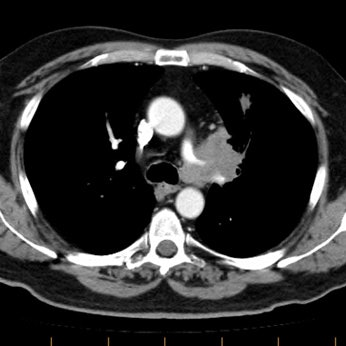

Example 2: This patient with non-small cell lung cancer demonstrates many findings which are suspicious for mediastinal invasion. There is greater than 3 cm of contact between the mass and the mediastinum, loss of the mediastinal fat plane between the mass and the left pulmonary artery, deformity of the left pulmonary artery, and pericardial thickening (yellow arrows). The patient also demonstrates contralateral mediastinal adenopathy (N3 nodes -- white arrow), subcarinal adenopathy (SC), and bilateral pleural effusions.

NOTE: Click image to enlarge